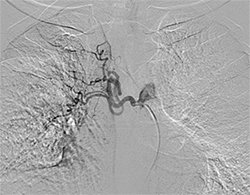

Procedure in which the blood supply of abnormal and diseased part of lung is blocked with medicine. A small puncture is made in blood vessel of thigh region with needle through which wire passed and sheath placed. Angiography done with catheter under X-ray guidance.